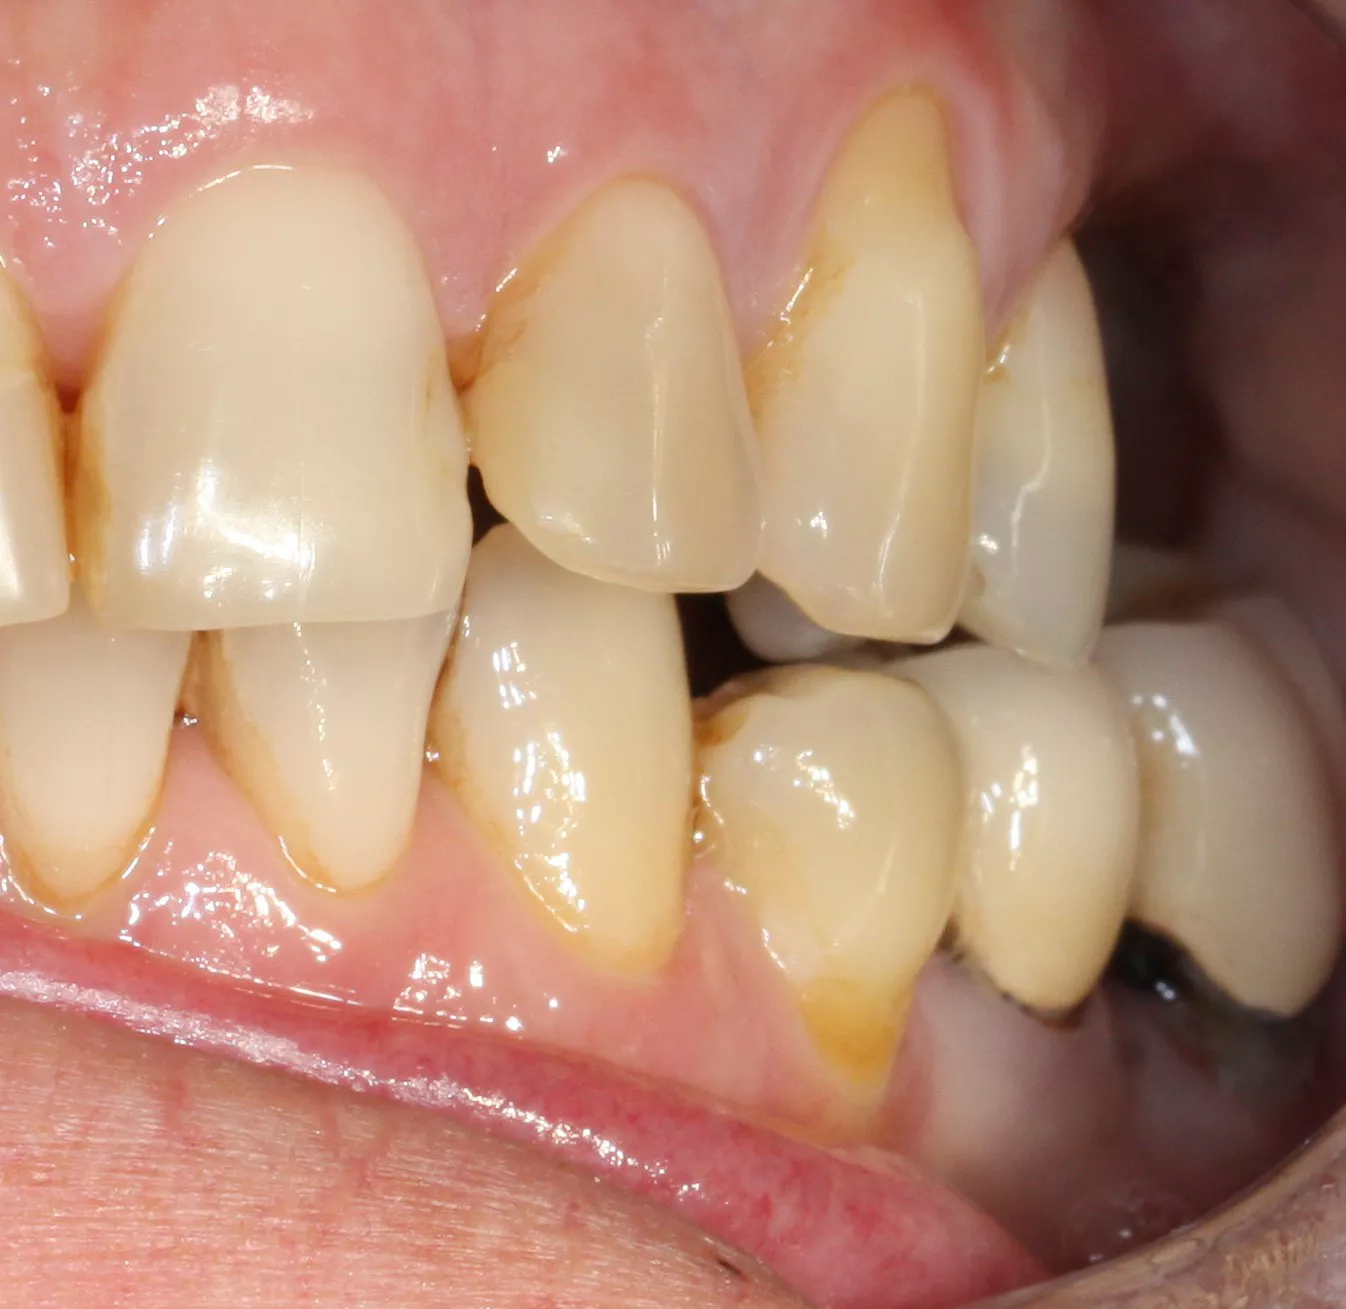

19. Final prosthesis in the mouth 3 years post implant placement.